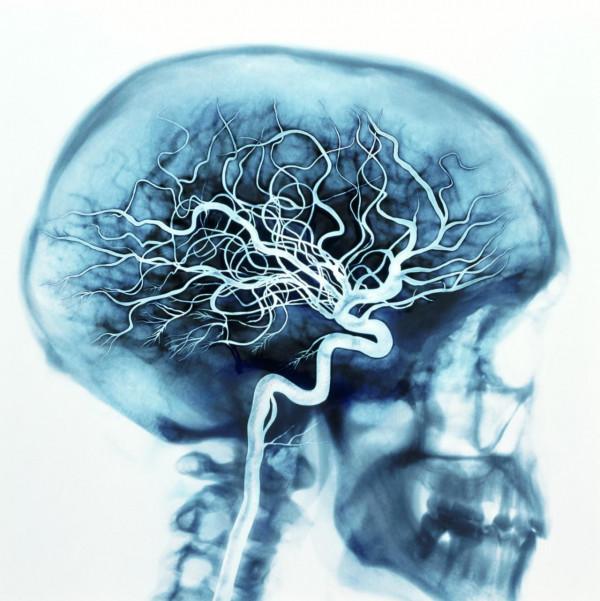

如果您是腦科醫生的話,那麼一定知道莫尼茲醫生是腦動脈血管造影術的發明者,1927年6月28日,他將碘鈉溶液注入頸動脈,成功對腦動脈進行了造影,“我們第一次看到了人類大腦動脈的活體射線照片。在X光片上,我們可以看到腫瘤使大腦動脈發生了扭曲。”

儘管事後患者由於過量的造影劑以及長時間的頸動脈結紮造成了血栓栓塞,最終於次日死亡,但莫尼茲醫生無疑開啟了腦血管造影術的大門,並於此將稀釋後的碘鈉溶液成功造影,並且不影響患者健康。